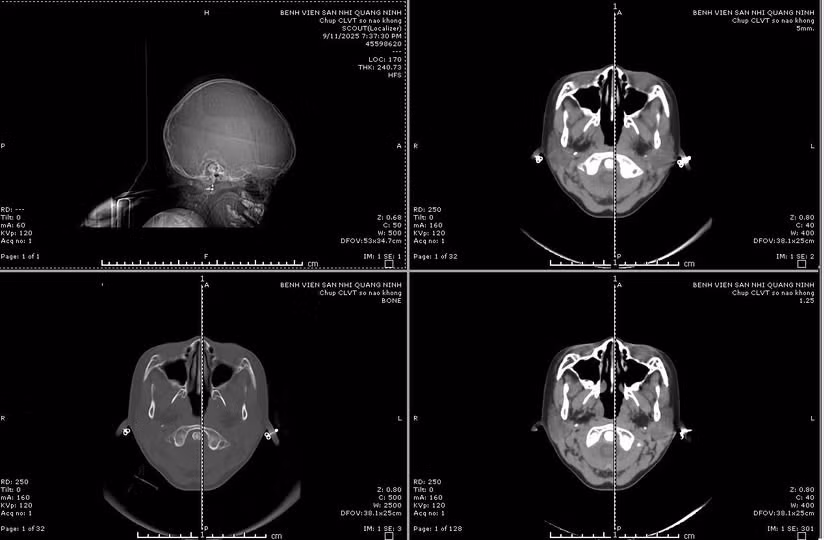

Sau khi tiếp nhận, bệnh viện đã kích hoạt quy trình báo động đỏ toàn viện, trẻ được các bác sĩ đã nhanh chóng xử trí hồi sức, cấp cứu suy hô hấp, cấp cứu ngừng tim, ngừng tuần hoàn, chăm sóc tích cực và thực hiện các cận lâm sàng. Kết quả cho thấy trẻ bị vỡ xương sọ phức tạp, kèm theo chảy máu và dập não phức tạp.

Các bác sĩ chuyên ngành ngoại thần kinh nhi của Bệnh viện Sản Nhi đã tiến hành phối hợp hội chẩn liên viện với chuyên gia ngoại thần kinh của Bệnh viện Đa khoa tỉnh; Trẻ được chẩn đoán bị xuất huyết nội sọ do chấn thương sọ não, tăng áp lực nội sọ, suy hô hấp và nhanh chóng được chuyển phòng mổ chỉ định mổ cấp cứu chấn thương sọ não.

so-nao-nang.jpg

Hình ảnh phim chụp chấn thương sọ não nặng - Ảnh BVCC